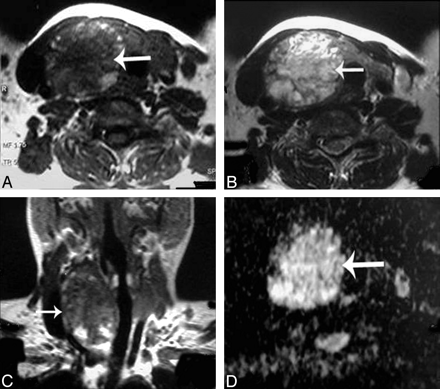

Table 1 illustrates the ADC values of the different histopathologic types of solitary thyroid nodules in this study. The ADC value of the adenomatous nodules ranged from 1.1 to 1.9 × 10−3 mm2/s (Fig 2). Also, the range of the ADC value of the solid part of the follicular adenoma was 1.2–2 × 10−3 mm2/s (Fig 3). The thyroid cysts (Fig 4) revealed the highest mean ADC value (1.9 ± 0.38 × 10−3 mm2/s) apart from 1 patient with hemorrhagic cyst (Fig 5), whose ADC value was 0.5 × 10−3 mm2/s, simulating malignant lesions. The malignant thyroid nodules showed lower ADC values (Figs 6 and 7). The mean ADC value of papillary carcinoma was 0.68 ± 0.23 × 10−3 mm2/s, and that of follicular carcinoma was 0.77 ± 0.17 ×10−3 mm2/s.

Adenomatous nodule. A–C, Axial T1- and T2-weighted and coronal T1-weighted MR images of the neck, respectively, showing a well-defined oval mainly solid solitary nodule (arrow) affecting the right thyroid lobe with contralateral tracheal displacement. D, An ADC map image with hyperintensity of the nodule (arrow) denoting increased diffusion and a measured ADC value of 1.57 ± 0.11 × 10−3 mm2/s.